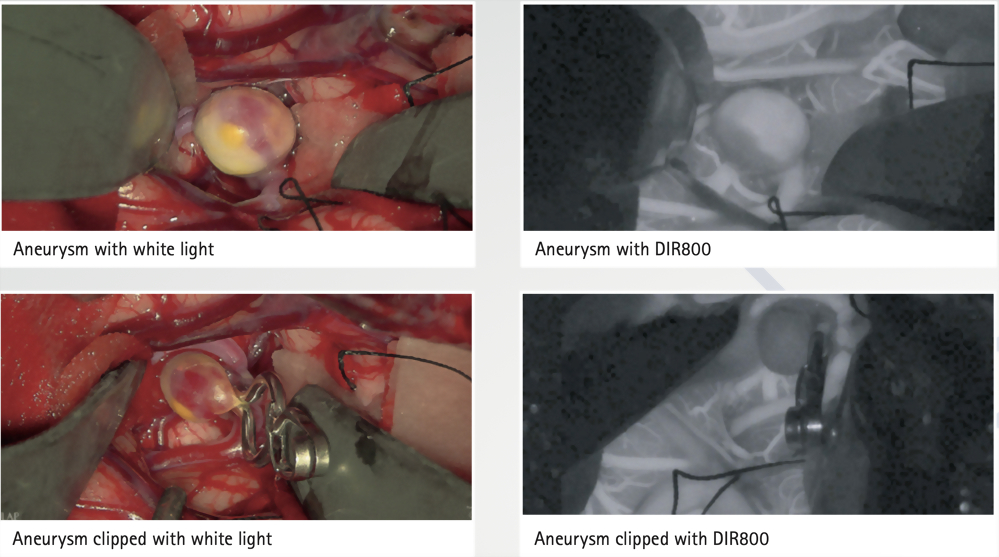

Aesculap Aeos® 是新世代數位手術顯微鏡系統,以先進的機器人技術和高清晰度的 3D 4k視覺效果聞名,有最先進的光學影像技術和精準的Robatic操作系統,提供無與倫比的顯微手術視覺感體驗。

Aesculap Aeos®擁有優異的放大倍率與景深效果、精確對焦和無影樣式的光學鏡頭,機器人自動定位提供外科醫生更精準與清晰的3D手術視野。